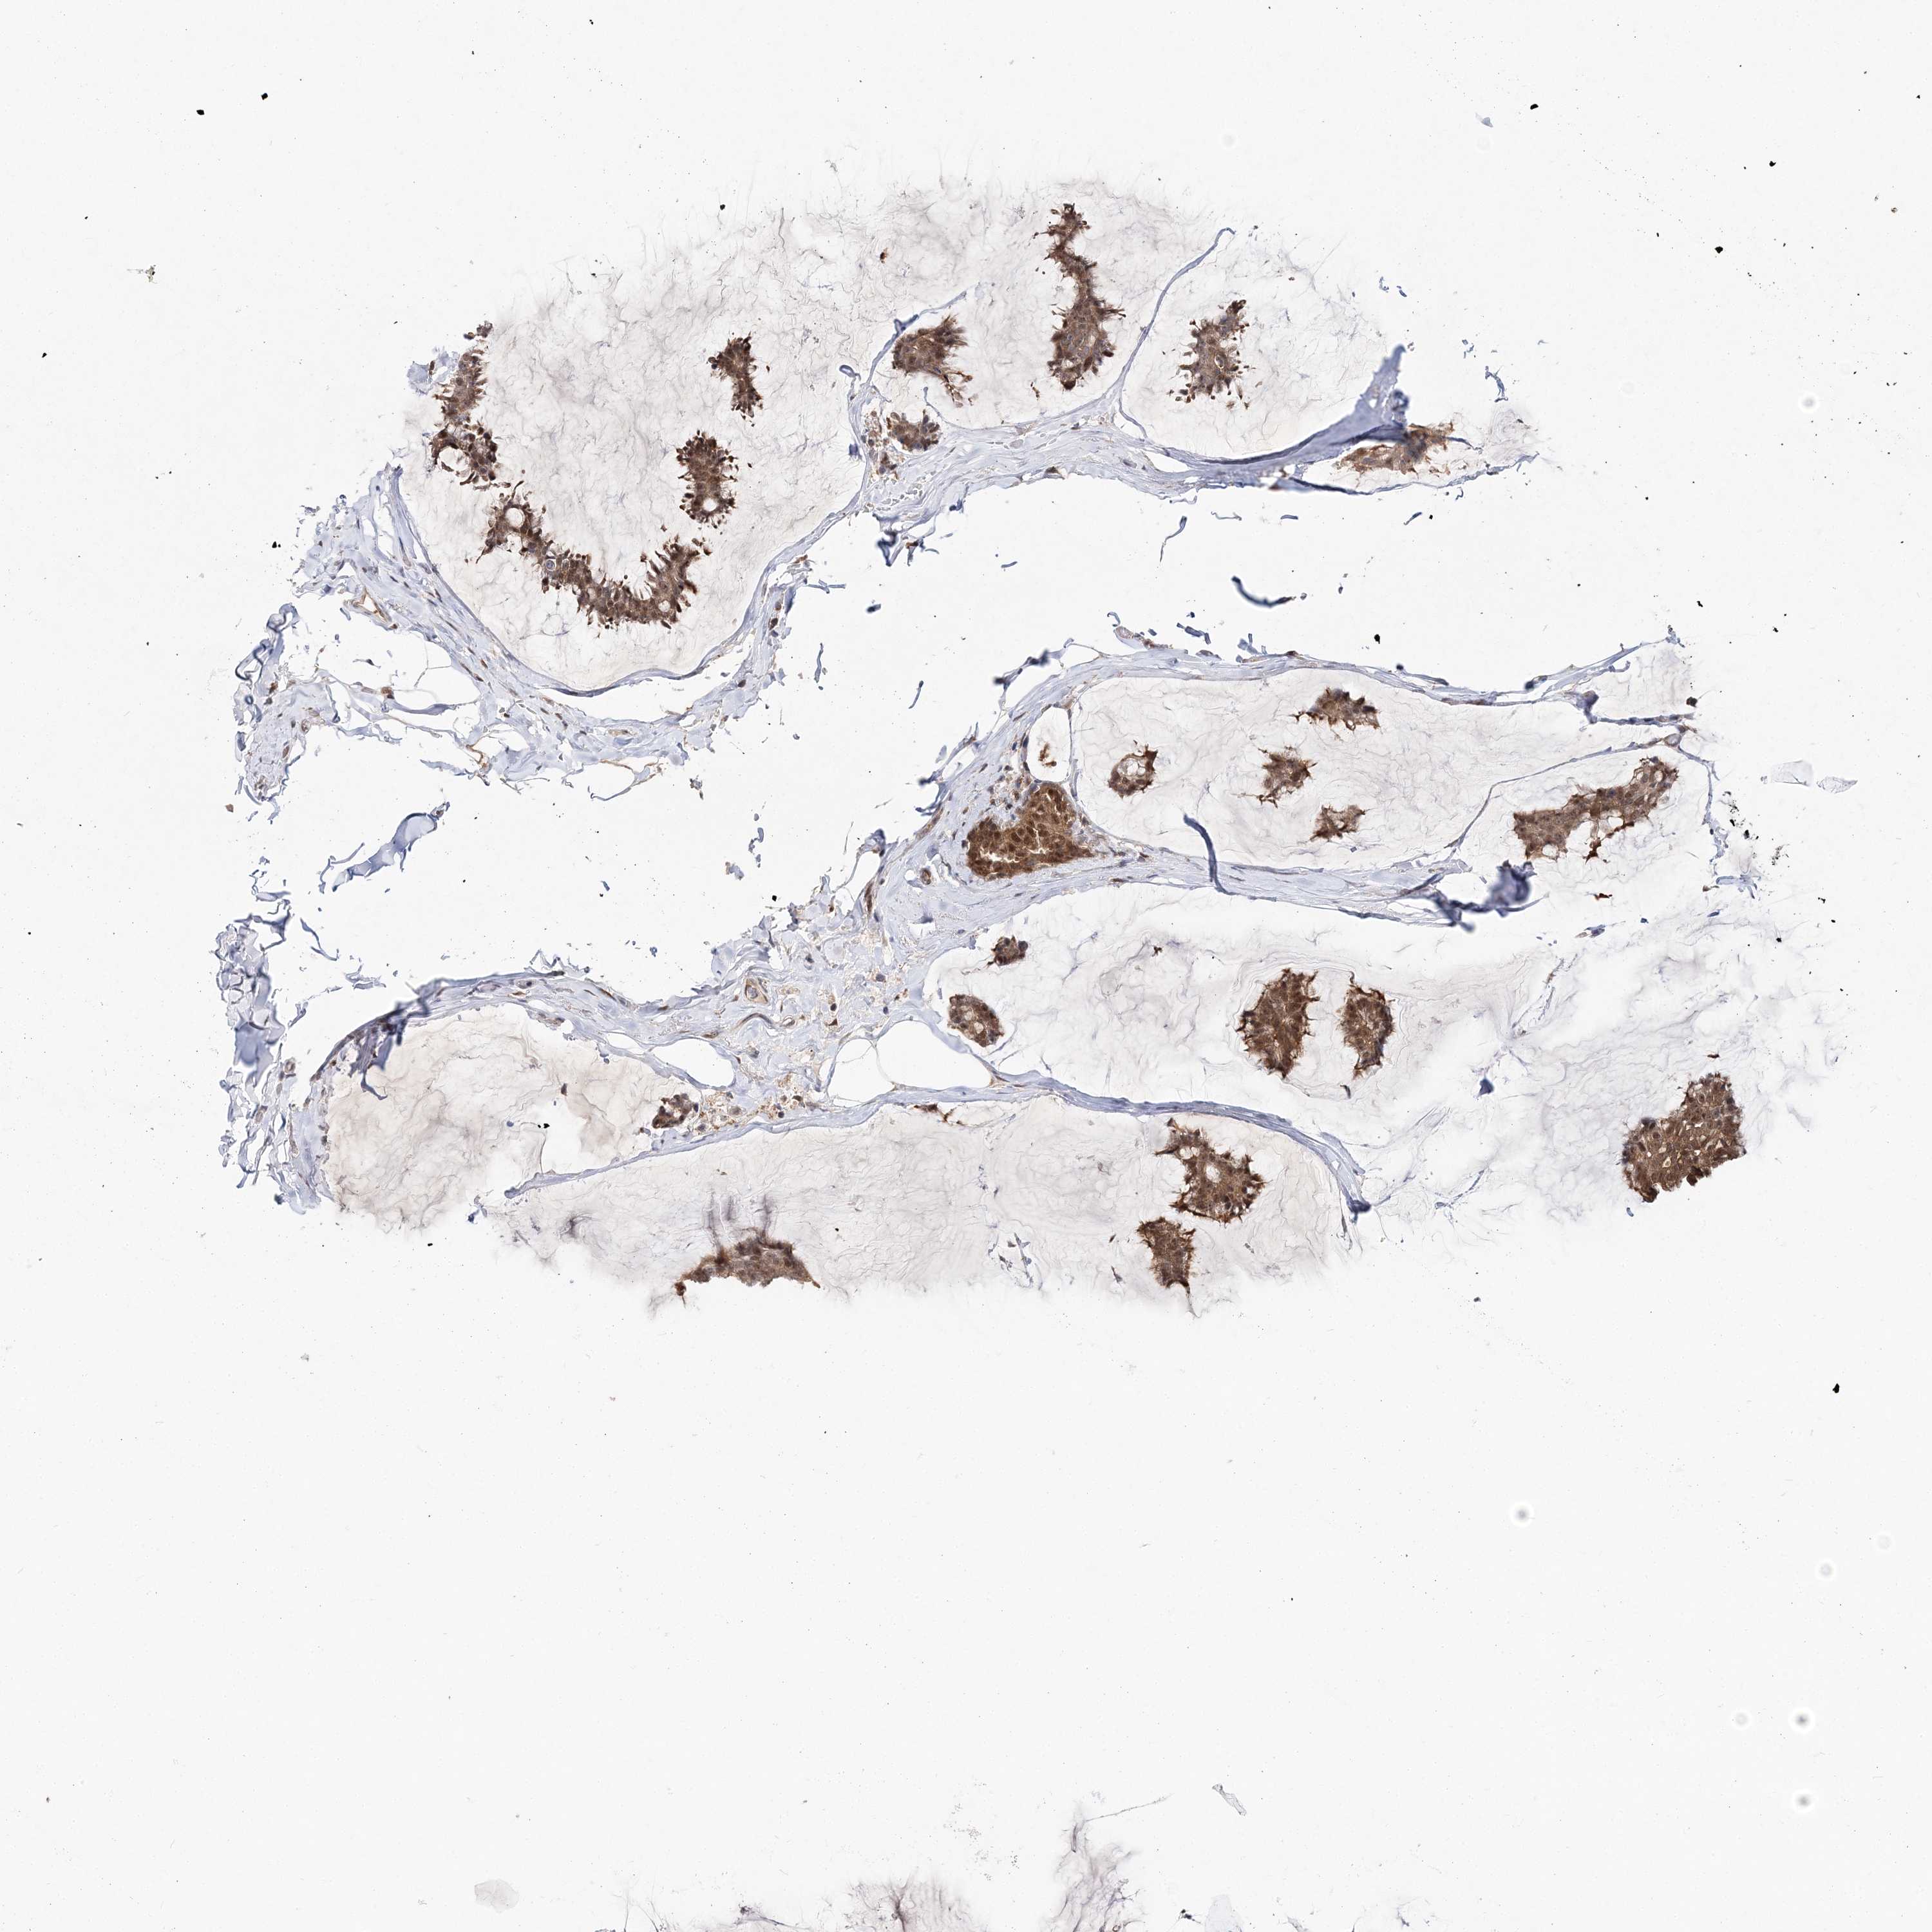

CANCER BREAST CANCER Show tissue menu

BRCA TCGA BRCA VALIDATION PROTEIN EXPRESSION